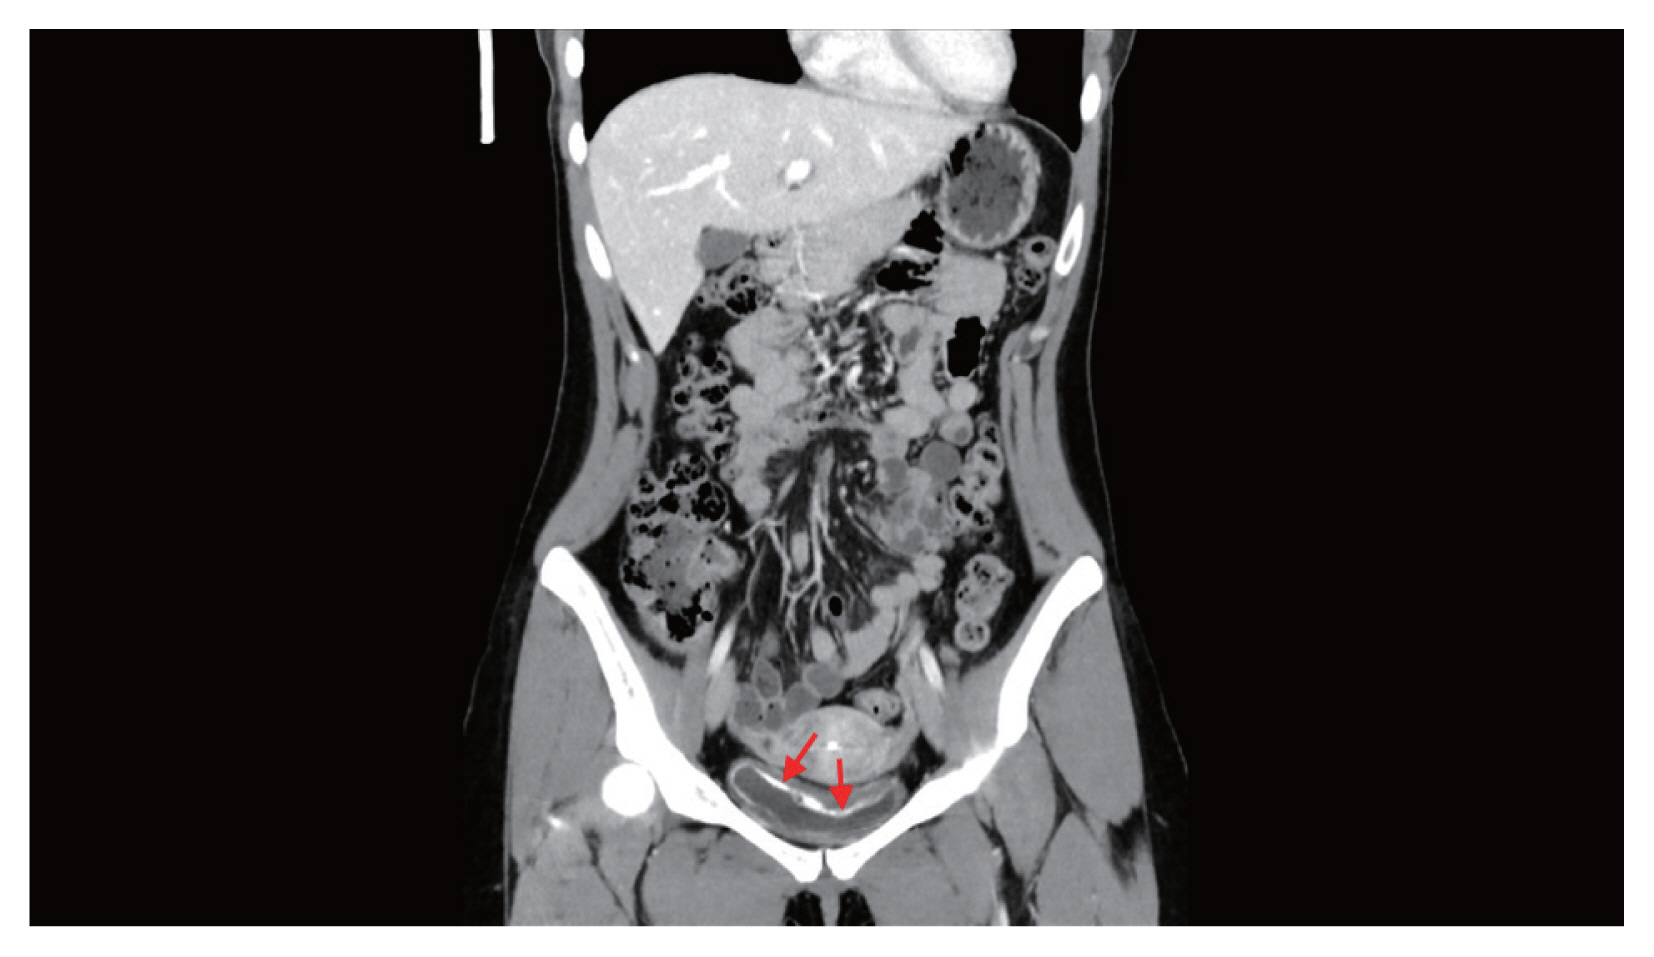

Hematuria had been continued at the time of admission. Urinalysis showed hematuria, proteinuria, and pyuria with a positive nitrite result. In urine cytology, abnormal findings were not identified. Blood tests revealed eosinophilia (1,129/μl, 19.5%) without anemia (hemoglobin 13.2 g/dl). Asymmetrically diffuse mucosal wall thickening and calcification were observed at the urinary bladder on pelvic CT (Fig. 1). Multiple erythematous nodular lesions and hemorrhage at the urinary bladder mucosa were observed in the cystoscopy and transurethral resection was performed for the histopathologic examination for the lesions (Fig. 2).